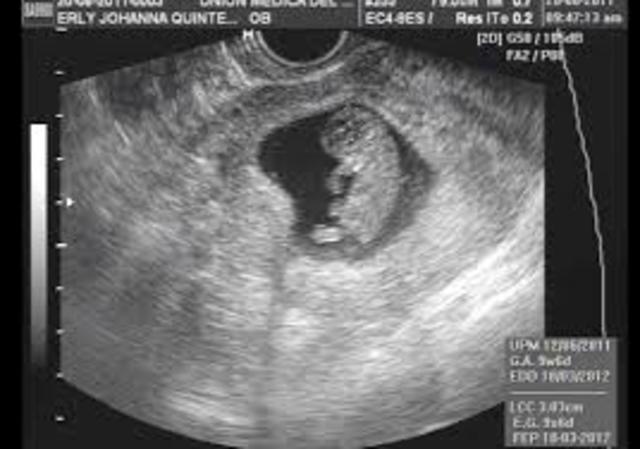

• 9 semanas Características externas

9 semanas Características externas

-El cuello se desarrolla y el mentón se separa del tórax

-La flexión craneal es de cerca de 22 grados

-El corion se divide en liso y frondoso

-Los párpados se encuentran y se fusionan

-Los genitales externos empiezan a mostrar especificidad de género